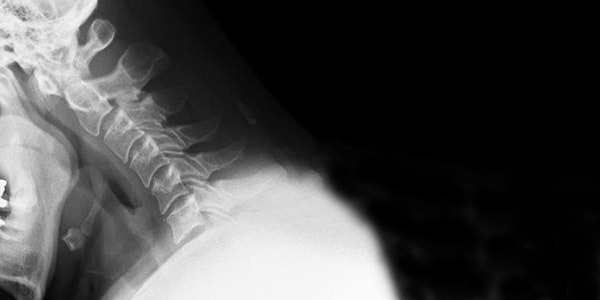

「頚椎症性神経根症」とは?

腕に伸びる神経は首(頚椎)より枝分かれして伸びていますが、その頚椎の出口である 椎間孔が何らかの原因で狭くなる事で神経根を圧迫すると、腕に痺れや痛みが走ります。

そのため、上を向く動作や、後を振り向く動作は椎間孔を狭くするため、症状が強くでます。